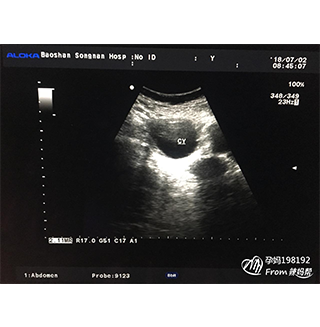

NT(nuchal translucency),即頸項(xiàng)透明層,是指胎兒頸椎水平矢狀切面皮膚至皮下軟組織之間的大厚度。NT檢查又稱(chēng)頸后透明帶掃描,是通過(guò)B超手段測(cè)量胎兒頸項(xiàng)部皮下無(wú)回聲透明層厚的部位,用于評(píng)估胎兒是否有可能患有唐氏綜合征的一種方法。

寶寶頸后透明帶為6毫米,具有很高的唐氏綜合癥以及其它染色體、遺傳綜合癥和心臟問(wèn)題的風(fēng)險(xiǎn)。